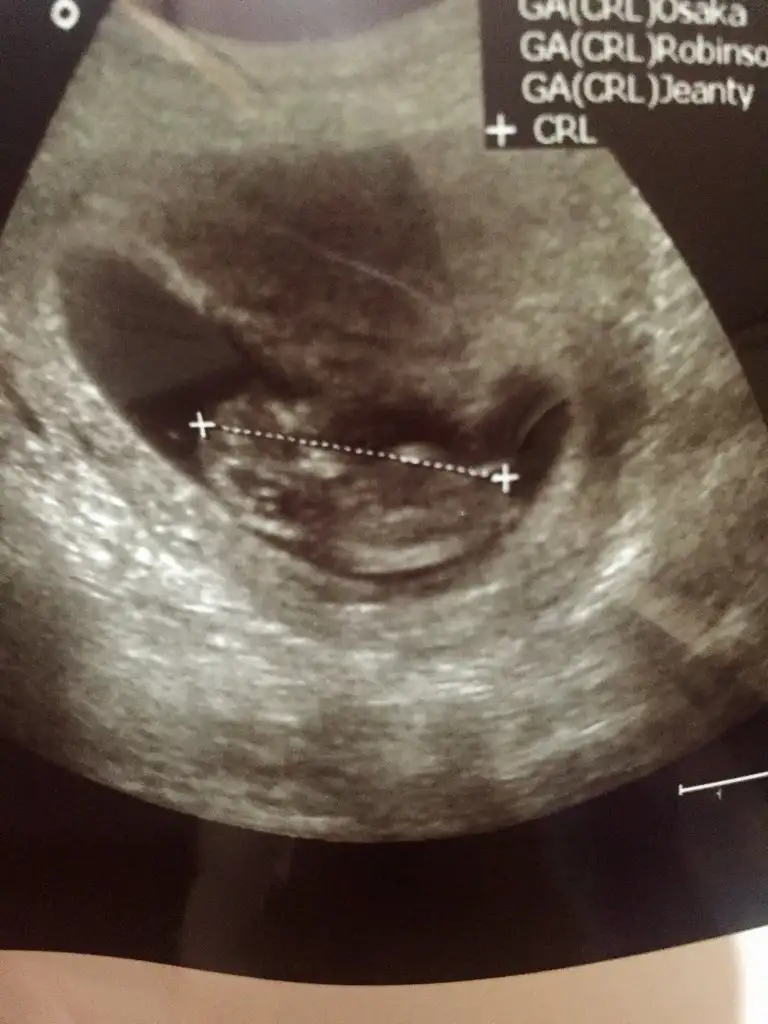

Selamın aleyküm kızlar ben geldim bu da bnm bebişim 11+3 ultrasonu dr tahminde bulundu ama sizler ne diyeceksiniz merak ettim

Eklentiler

• 4C91DEA8-BF47-4EDD-BE91-741576B1995B.webp

30,9 KB · Görüntüleme: 83